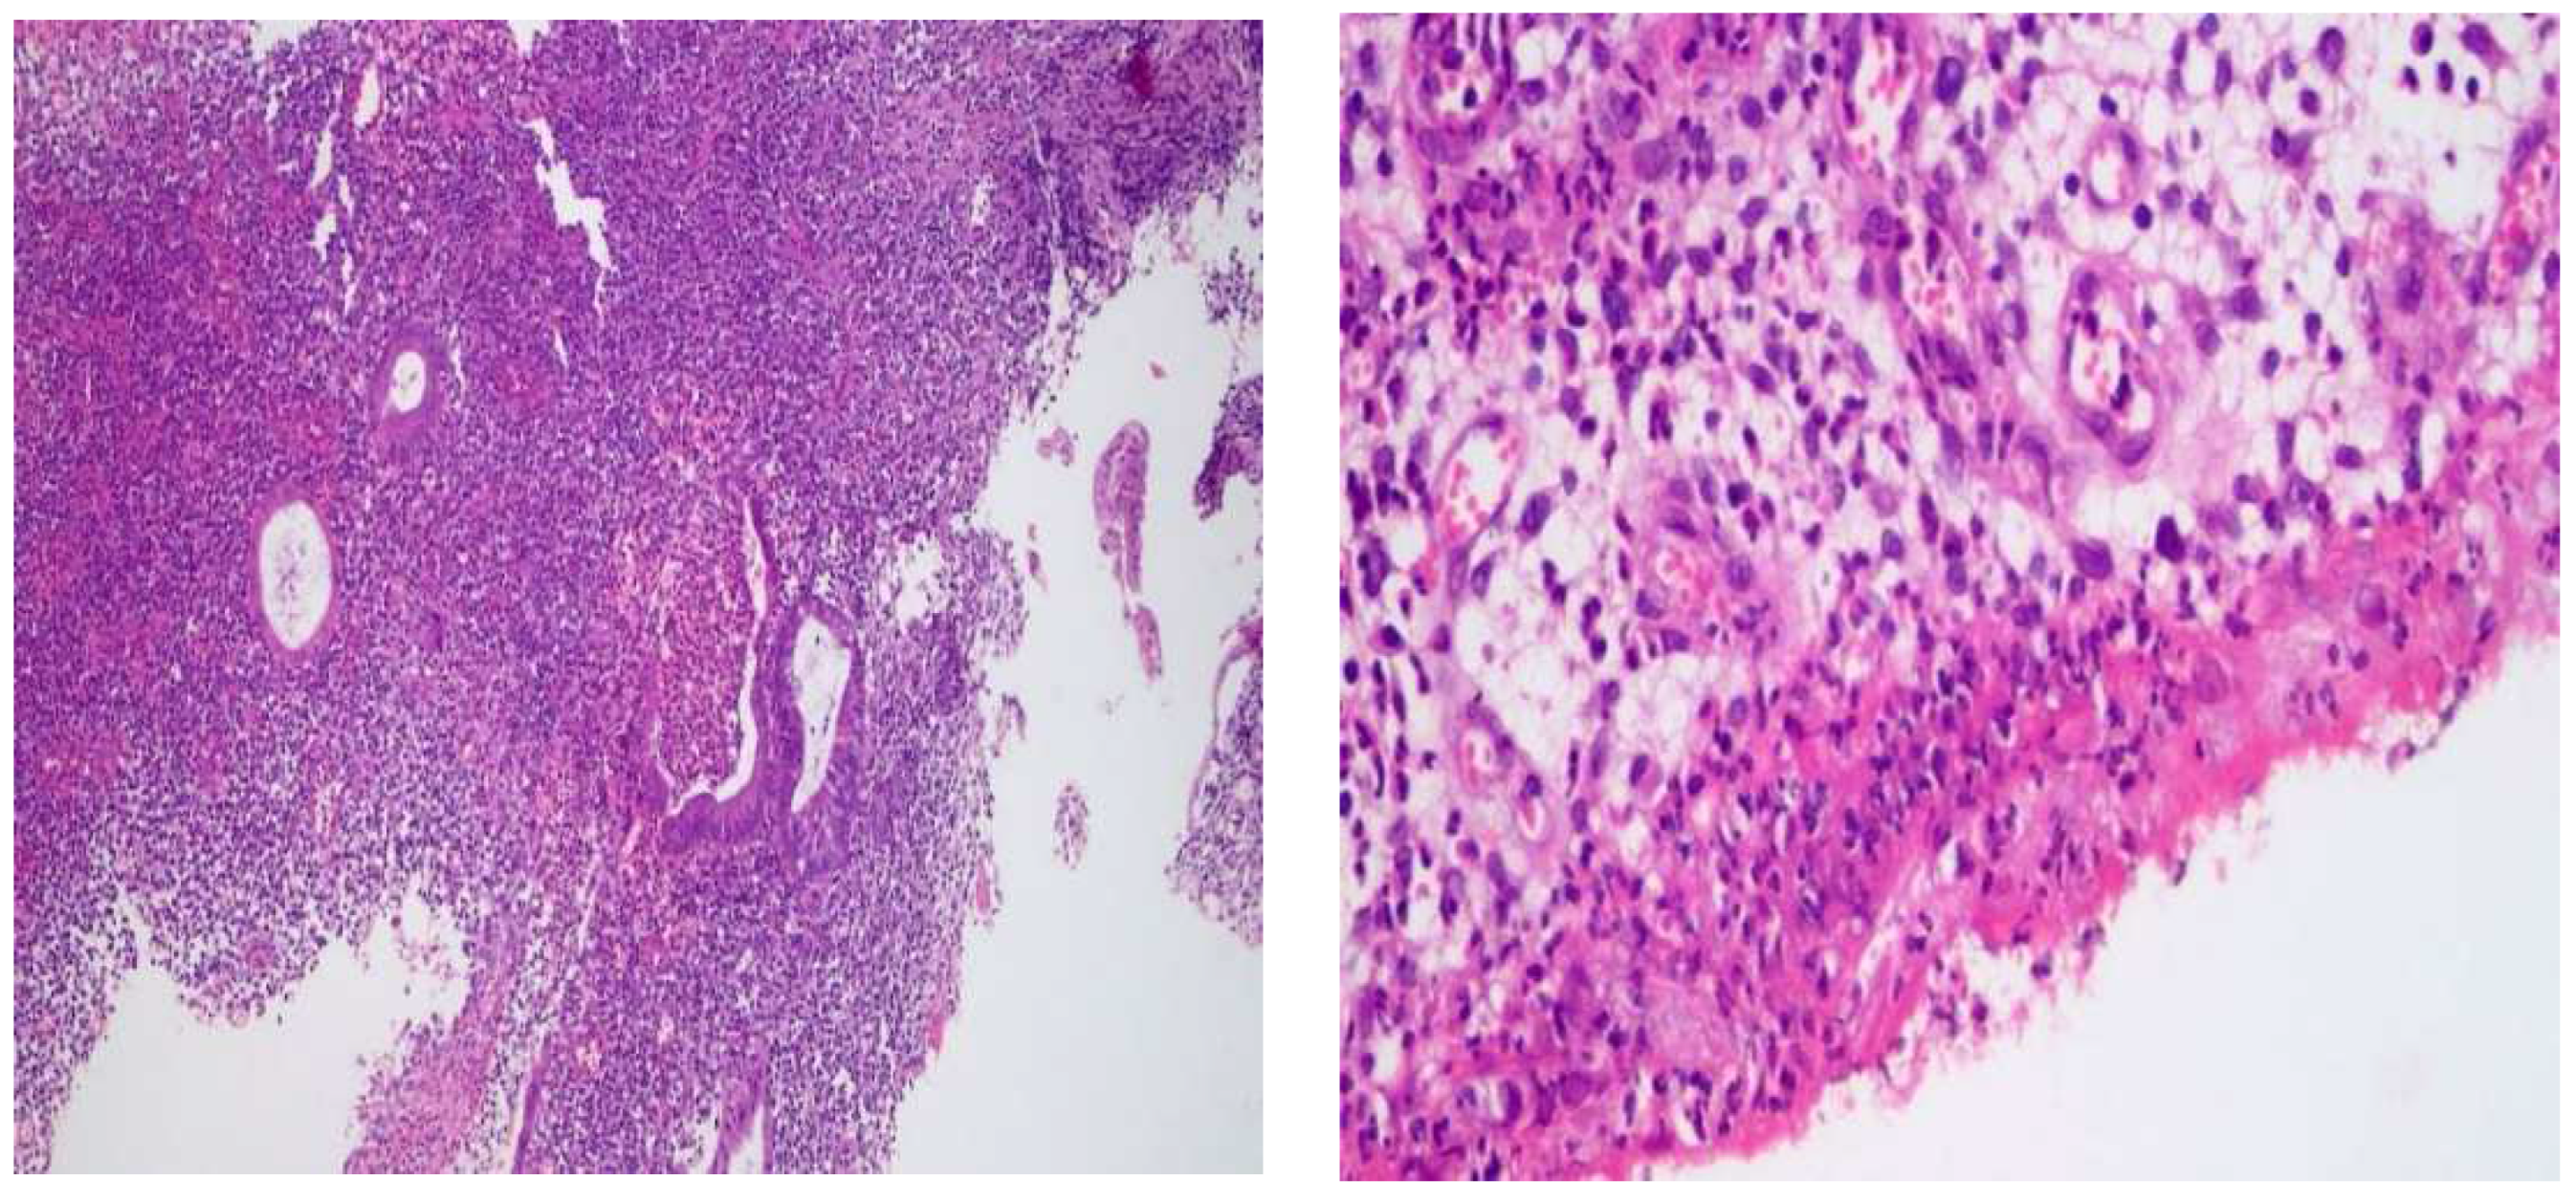

2.1. Histological Changes